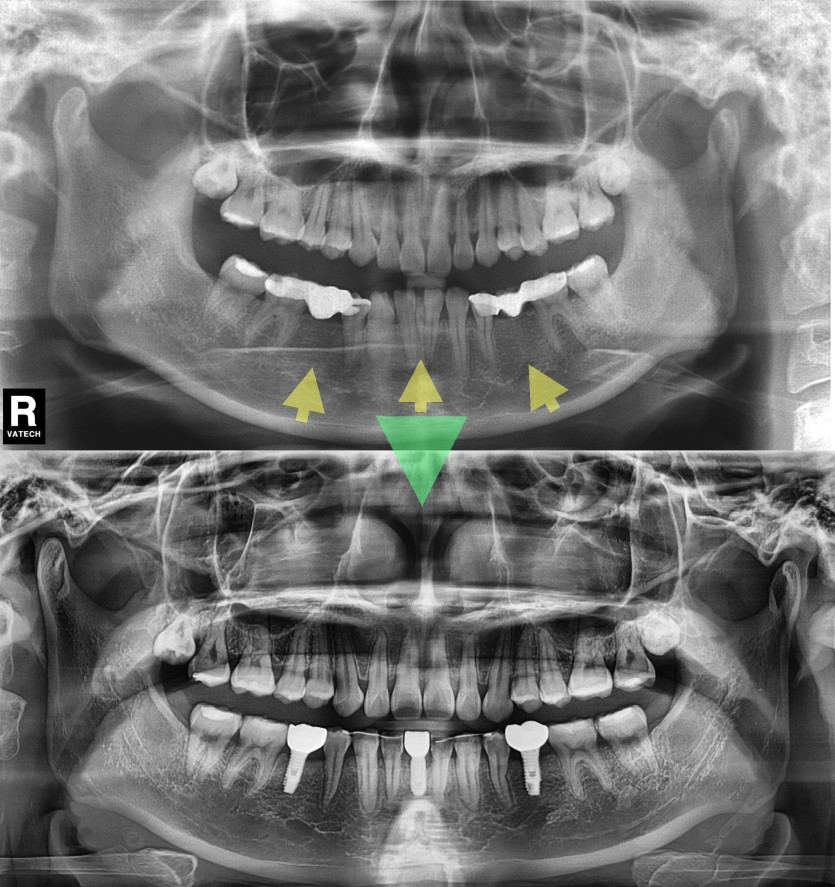

임플란트를 위한 교정치료 250회

치아가 결손된 경우에는 결손된 공간으로 치아들이 움직이면서 흩어져서

결손된 공간에 임플란트를 바로 심지 못하는 경우가 대부분입니다 .

결손된 치아의 공간으로 흩어진 공간을 모아주어야 하는 치료가 필요합니다.

심미와 기능을 회복하는 치료라고 할 수 있지요.

공간이 형성된 뒤 의뢰되었던 치과로 후속처치를 위해 다시 의뢰드리고 있습니다.